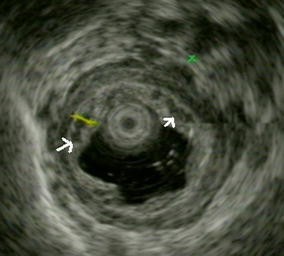

Endoscopic ultrasonography assessment of para-esophageal varices predicts efficacy of propranolol in preventing recurrence of esophageal varices

Volume of para-esophageal varices (PEV) correlates with esophageal varices recurrence. The effect of propranolol on volumetric change of PEV has not been studied. The relation between EV recurrence and volumetric change of PEV in patients undergoing endoscopic variceal ligation (EVL) with and without propranolol are studied.

Sixty-six patients who achieved EV eradication by primary EVL were randomly allocated to a propranolol group (n = 33) or control group (n = 33). The endpoints of the study were EV recurrence and volumetric change of PEV assessed by using endoscopic ultrasonography (EUS) at 3-month intervals for 2 years.

The cumulative probability of recurrence at two years was 28 % in the propranolol group (n = 9) and 68 % in the control group (n = 20) (p = 0.005, log-rank test). Difference of the volumetric change of PEV became significant as early as at the third month [−0.12 (−0.38–0.34) vs. 0.14 (−0.06–0.57), p < 0.001] between the two groups. Regression of PEV was achieved in 20 patients of the propranolol group at a median time of three months (range 3–12 months), and no EV recurrence was found at the end of follow-up for two years. On multivariate analysis, the volumetric change of PEV at the third month and use of propranolol were determinants of EV recurrence.

Propranolol may reduce both EV recurrence rate and volume of PEV in patients achieving endoscopic eradication. Regression of PEV is a predictor of durable eradication of EV without recurrence in patients using propranolol. EUS is an objective and useful tool to measure PEV and predict recurrence of EV.